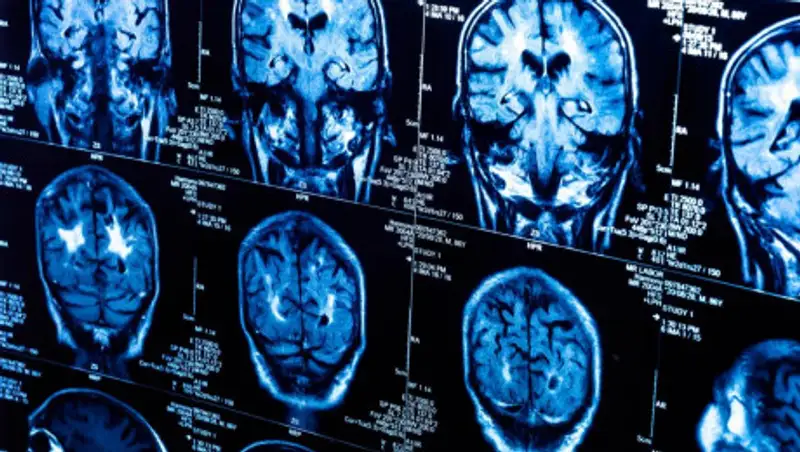

Глиобластома - это одна из самых опасных и "по сути неизлечимых опухолей".

Он также добавил, что глиобластома - это одна из самых опасных и "по сути неизлечимых опухолей".